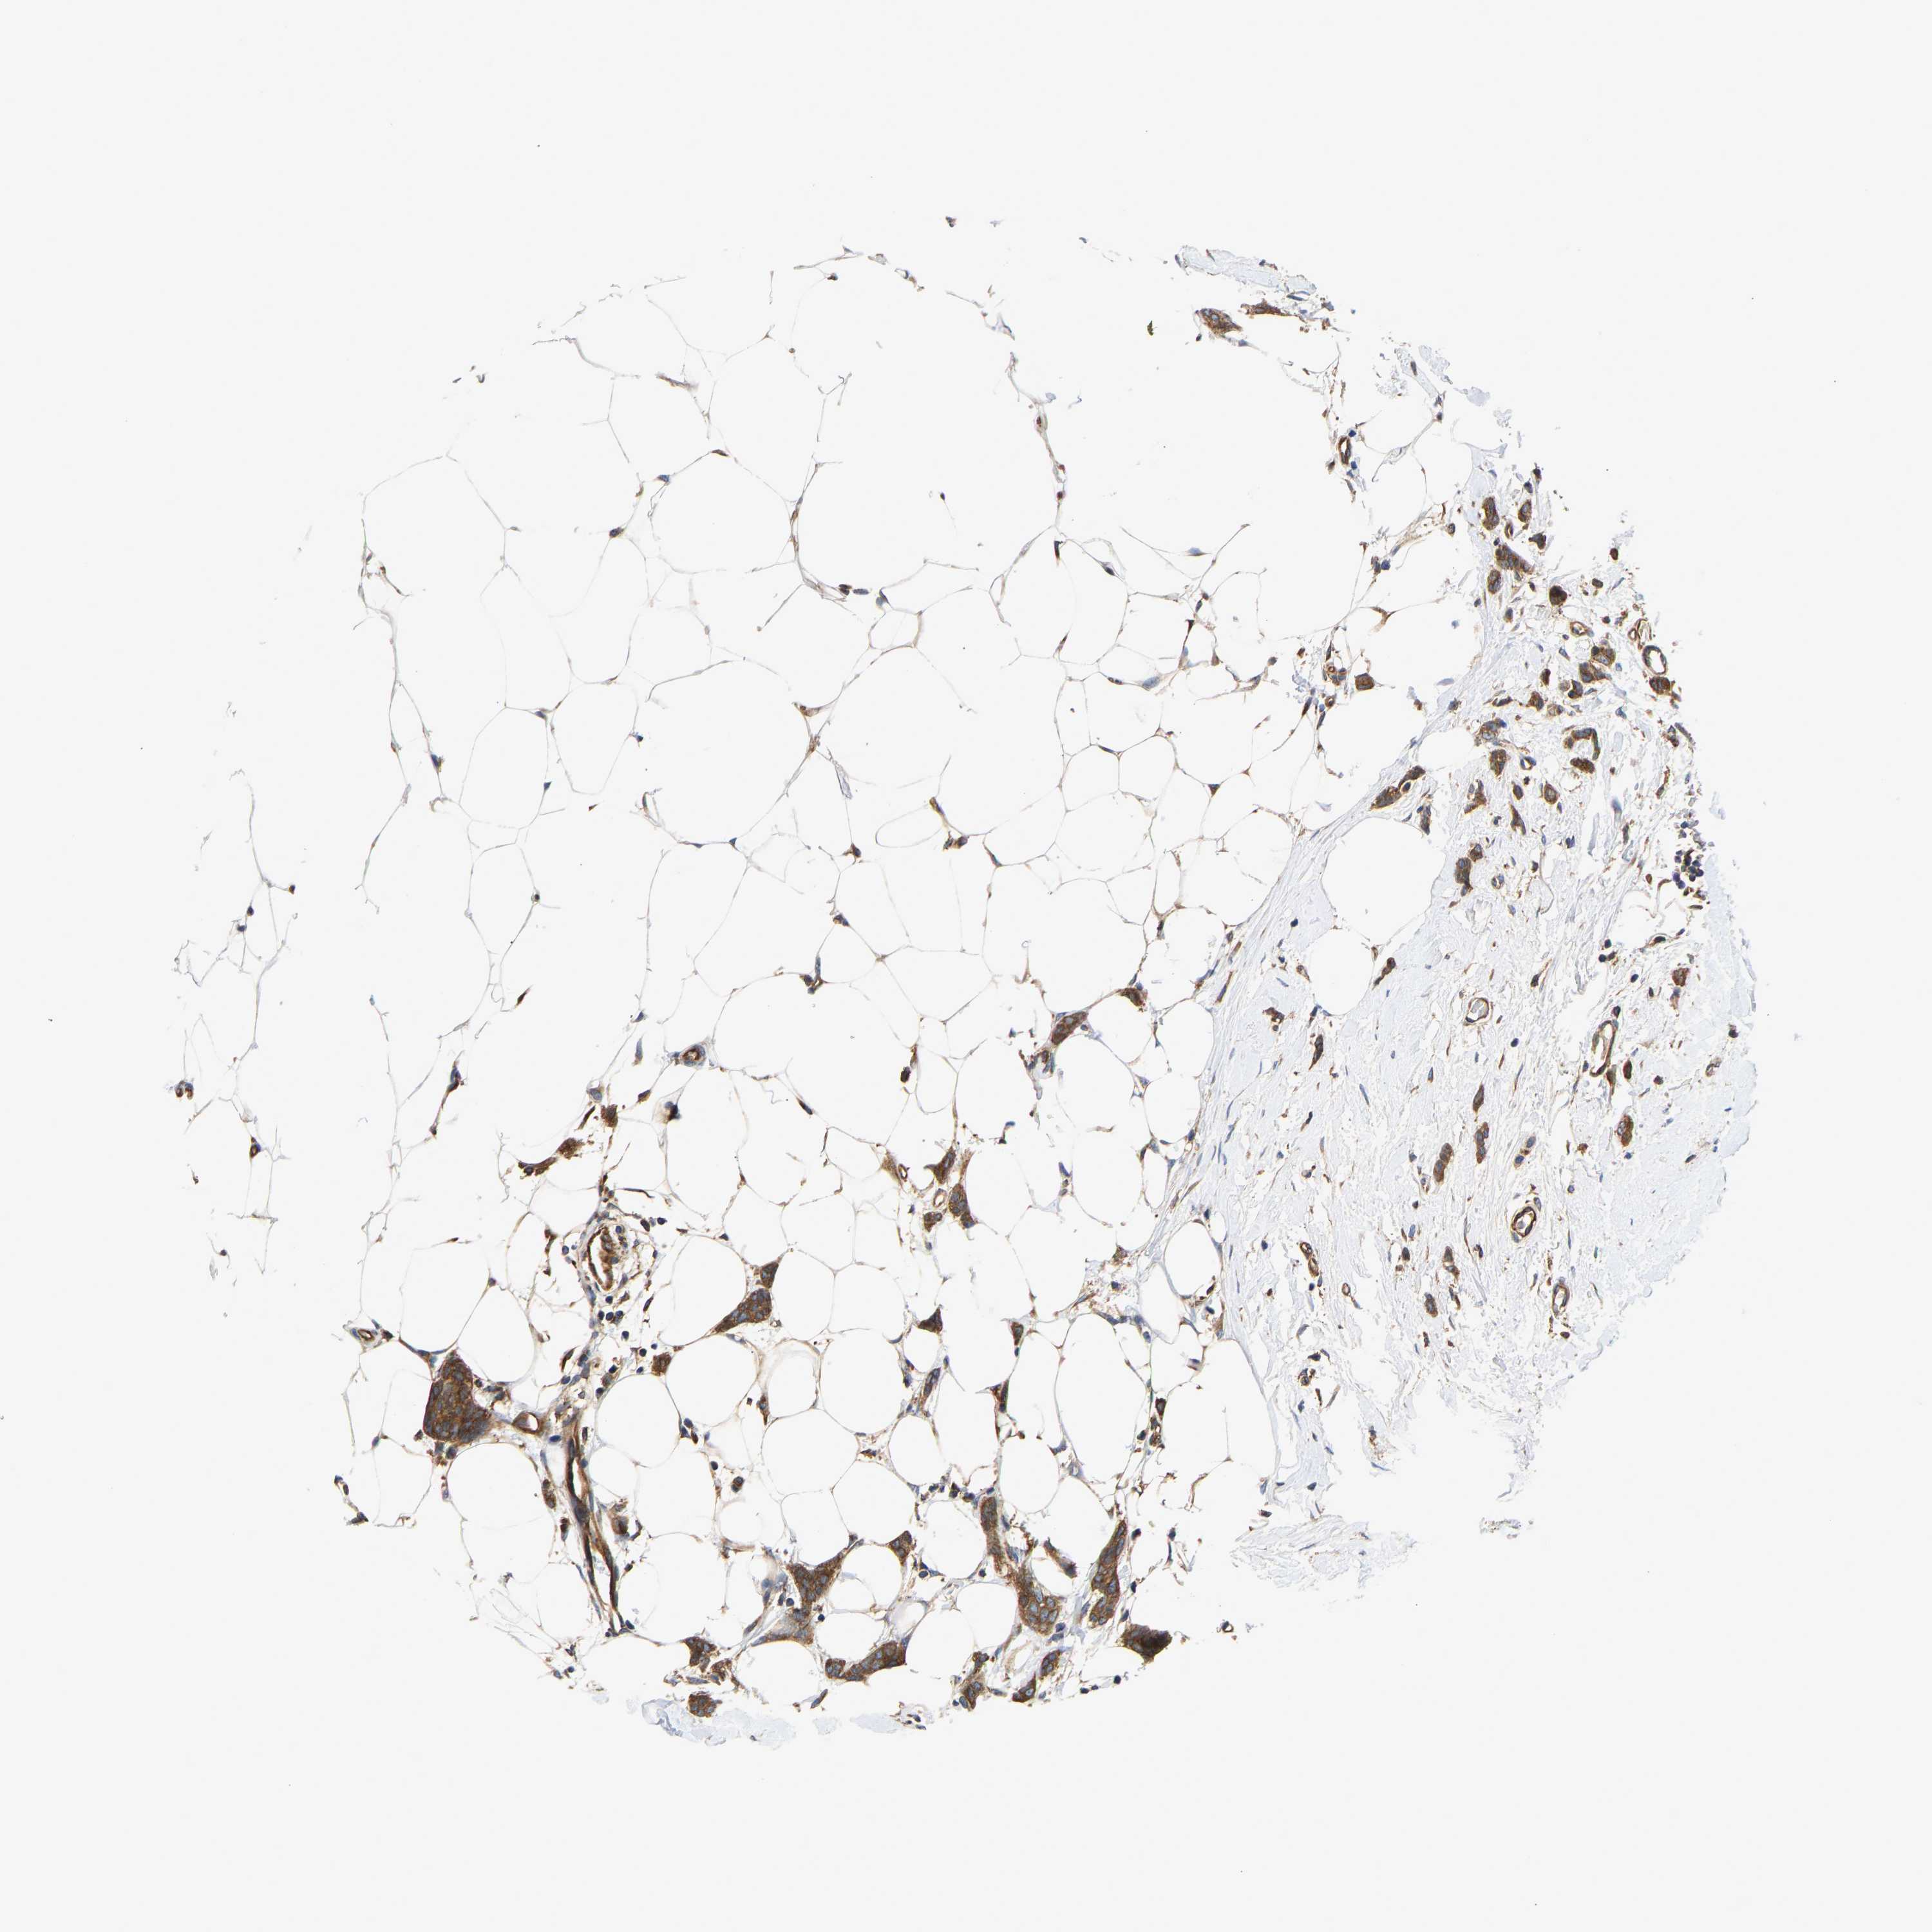

BRCA TCGA BRCA VALIDATION PROTEIN EXPRESSION